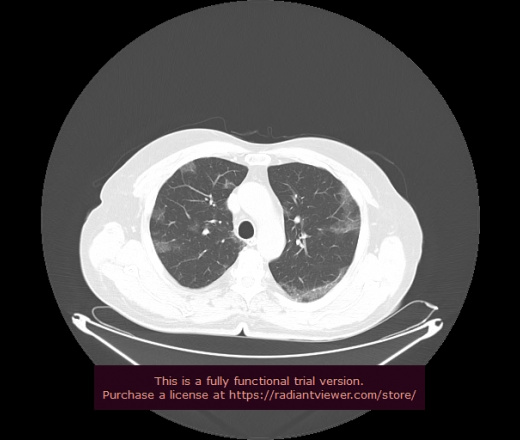

Уважаемые коллеги, если имеется интерес, сможете ли Вы спрогнозировать дальнейшее +-одинаковое течение процесса у 4 данных разных пациентов? Зацепиться где-то можно очень просто, где-то нельзя.